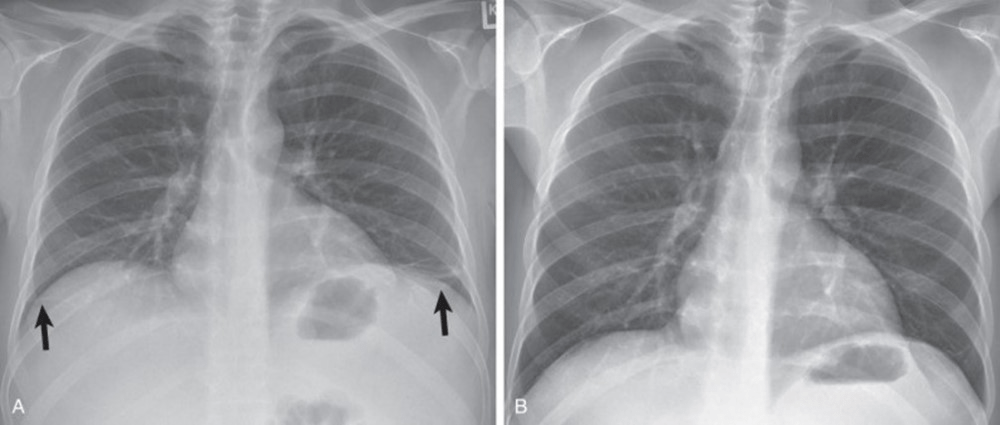

The CXR on the left is before treatment and the CXR on the right is after treatment. What has changed?

a. pulmonary edema has improved

b. the lungs have been expanded

c. free air in the pleural space has been removed

d. fluid in the pleural space has been drained